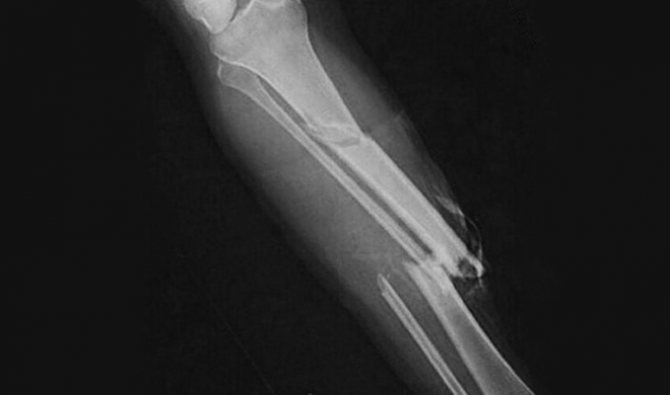

Запитання 17

ПЕРЕЛОМ ЯКОЇ КІСТКИ І ЯКОЇ ЇЇ ЧАСТИНИ ВИ БАЧИТЕ НА РИСУНКУ?

варіанти відповідей

ДИСТАЛЬНОГО ДІАФІЗА

HUMERUS

ULNA

RADIUS

ПРОКСИМАЛЬНОГО ЕПІФІЗА

ДИСТАЛЬНОГО ЕПІФІЗА

ДІАФІЗА

МЕТАФІЗА